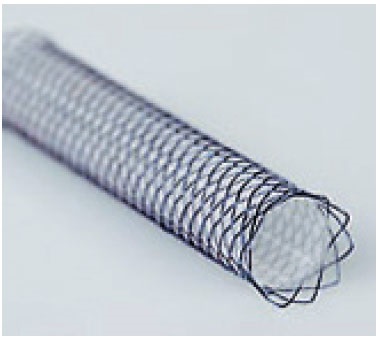

Endoluminális helyreállítása légcső keresztül önmagától táguló stent készült Nitinol (nikkel-titán ötvözet) használt a közelmúltban. Ez protézis eredetileg tervezett bővítése sérült artériák és epeutak emberekben. Az általunk használt biliáris stentek Nitinella, amelyeknek számos előnye van: atraumatikus végei csökkentse annak lehetőségét, traumás légcső fal, nagy szilárdságú ellenállás, jó kapacitás bővítését, könnyen implantáció, radiopak markerek mindkét végén a sztent (ris.11,12).

Mivel a Nitinol hajlékony és rugalmas, és fizikai tulajdonságai hasonlóak a porc, a légcső, a legtöbb önműködő sztentek készült nitinol. Nitinoit stent használunk állandó implantátumot, és ezért nagyon fontos, hogy válassza ki a megfelelő méretet. Az átmérő van kiválasztva viszonyítva a normál rész trachea átmérője. Tartós beültetés, az szükséges, hogy a stentet a nyálkahártya alatti réteg, ez okozza nyomást elhalása az epitéliumban, de nem okoz a migráció a stent, amely irritációt okozhat, és a termelés granulációs szövet vezető légúti elzáródás. A cél az, hogy a légcső túl a többit a sztent és vezetjük be a nyálkahártya alatti réteg. Fokozott nyugalmi tracheális átmérőjű 1-25-1.8 időt biztosít optimális tömörítés. Átmérőjének növelése kétszer vezethet negatív következményekkel jár a sztent behatolás a mélyebb rétegeibe a légcső és a nekrózis (13. ábra).

A telepítés után a stent a légcső ürege, a stent fokozatosan alkalmazkodik az üreg méretét a légcső. Az előnye ennek az eljárásnak, mint a műtéti stabilizálásra ¬sostoyat az, hogy nem invazív, és mindössze 5-10 perc, függően a gyakorlati képesség (ris.14,15).